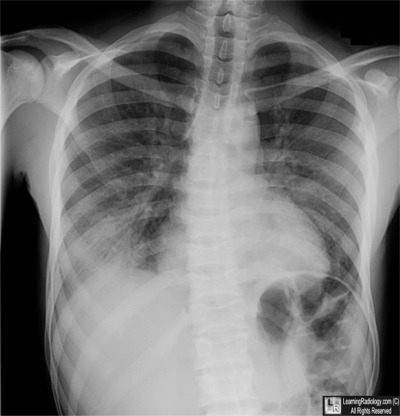

- 26 year-old with fever, shortness of breath

Frontal Chest Radiograph

2. Acute Chest Syndrome

Acute Chest Syndrome

- Leading cause of death in patients with sickle cell disease

- Syndrome is characterized by

- New airspace disease on chest x-ray, and one or more of the following:

- Fever (variable)

- Cough

- Sputum production

- Shortness of breath

- Hypoxia